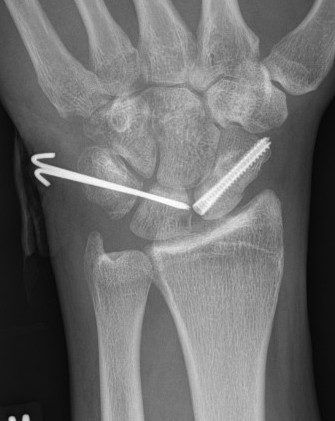

Perilunate fracture-dislocations / Trans-scaphoid perilunate

Dorsal approach

- ORIF scaphoid fracture with headless compression screws

- assess stability of scapho-capitate and scapholunte joint (often ligaments intact and stable)

- K wires lunate-triquetral +/-

- +/- repair LT ligament

- +/- ORIF capitate